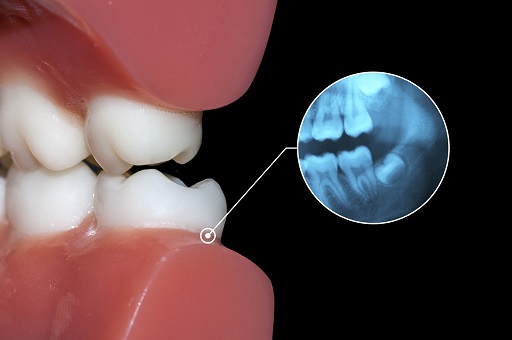

移植成功的智齿,能植根于牙龈中,达到“牙周膜愈合”。

这是什么概念?

牙周膜是牙齿和牙槽骨之间的一层致密组织,有丰富的神经末梢,能感知食物的大小、软硬,还能缓冲咀嚼对牙槽骨的冲击力。

有牙周膜,方有“咀嚼感”。

不少缺牙者使用活动假牙、种植牙后,觉得食之无味,就是因为缺了牙周膜。

优势2:坚固,不易损坏移植成功的智齿会保留牙周膜神经末梢,因此仍有知觉触感,会对咬到的过硬物产生避让反应,避免硬碰硬,损坏牙齿。